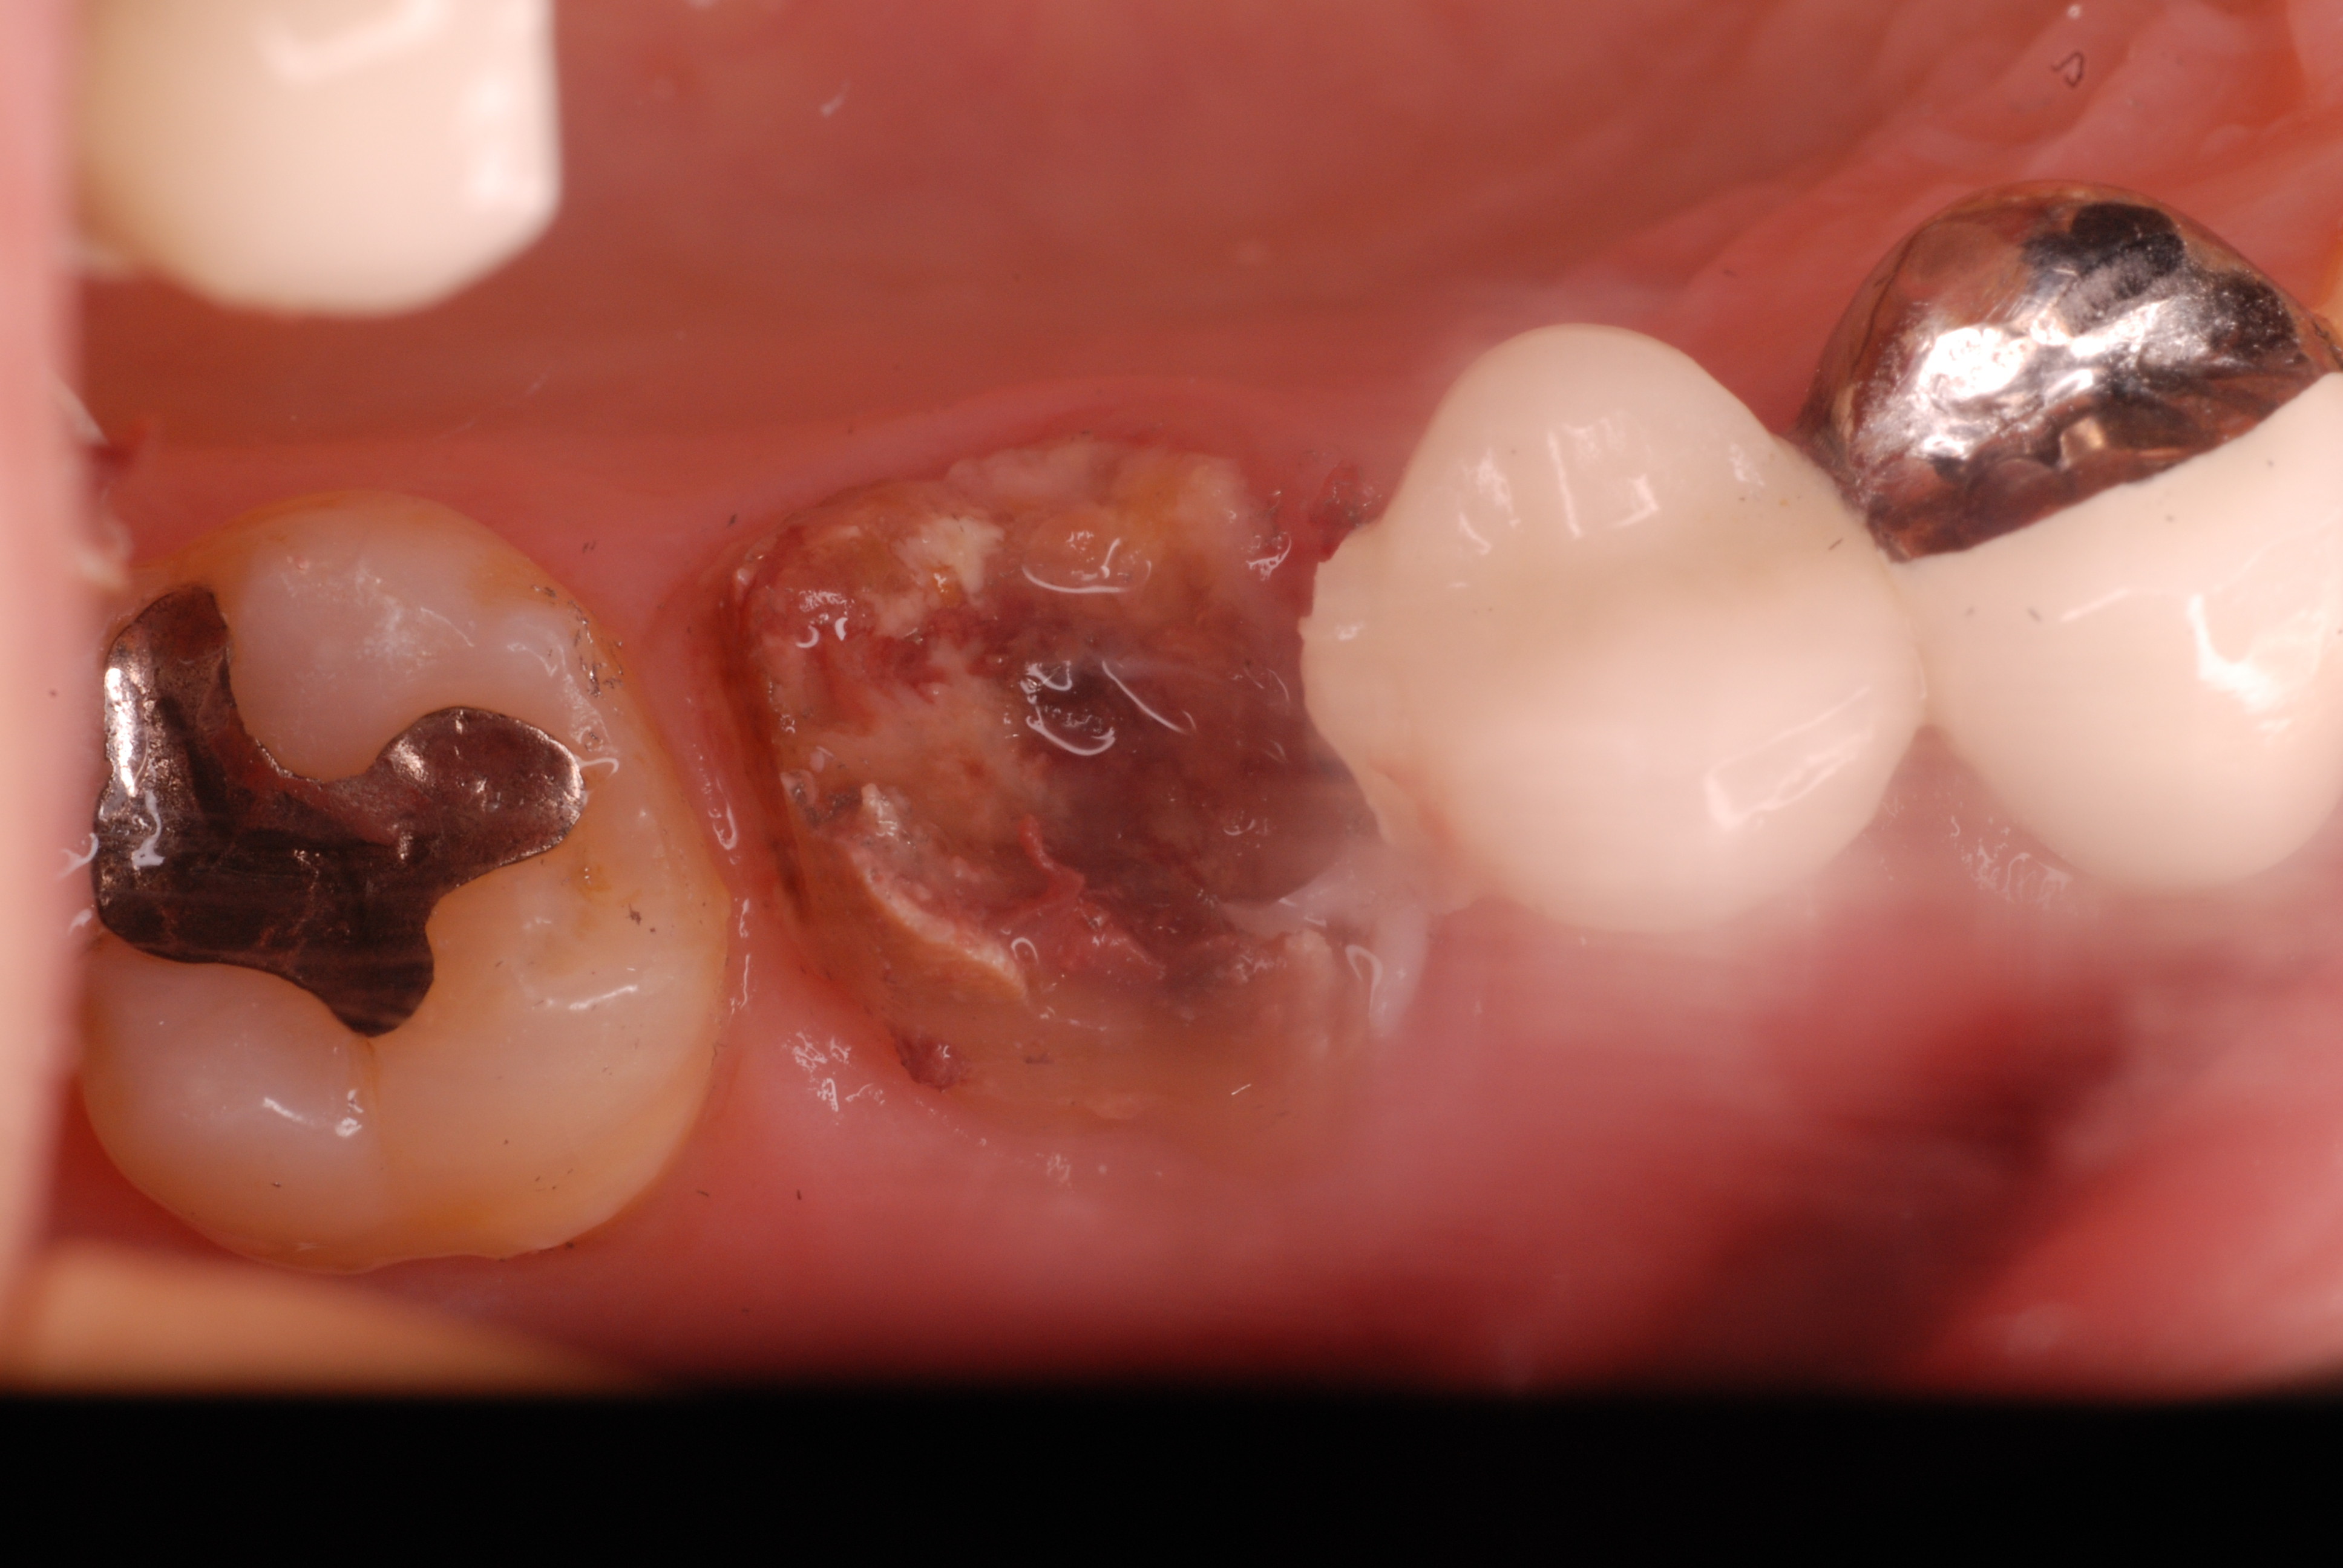

神経が死んでしまった歯は脆いのです。

重症の歯周病で削って上の歯とぶつからないようにしていた歯ですが

いつの間にか神経が死に歯の中が腐っていたようです。

それでヒビが入り割れてしまいました。